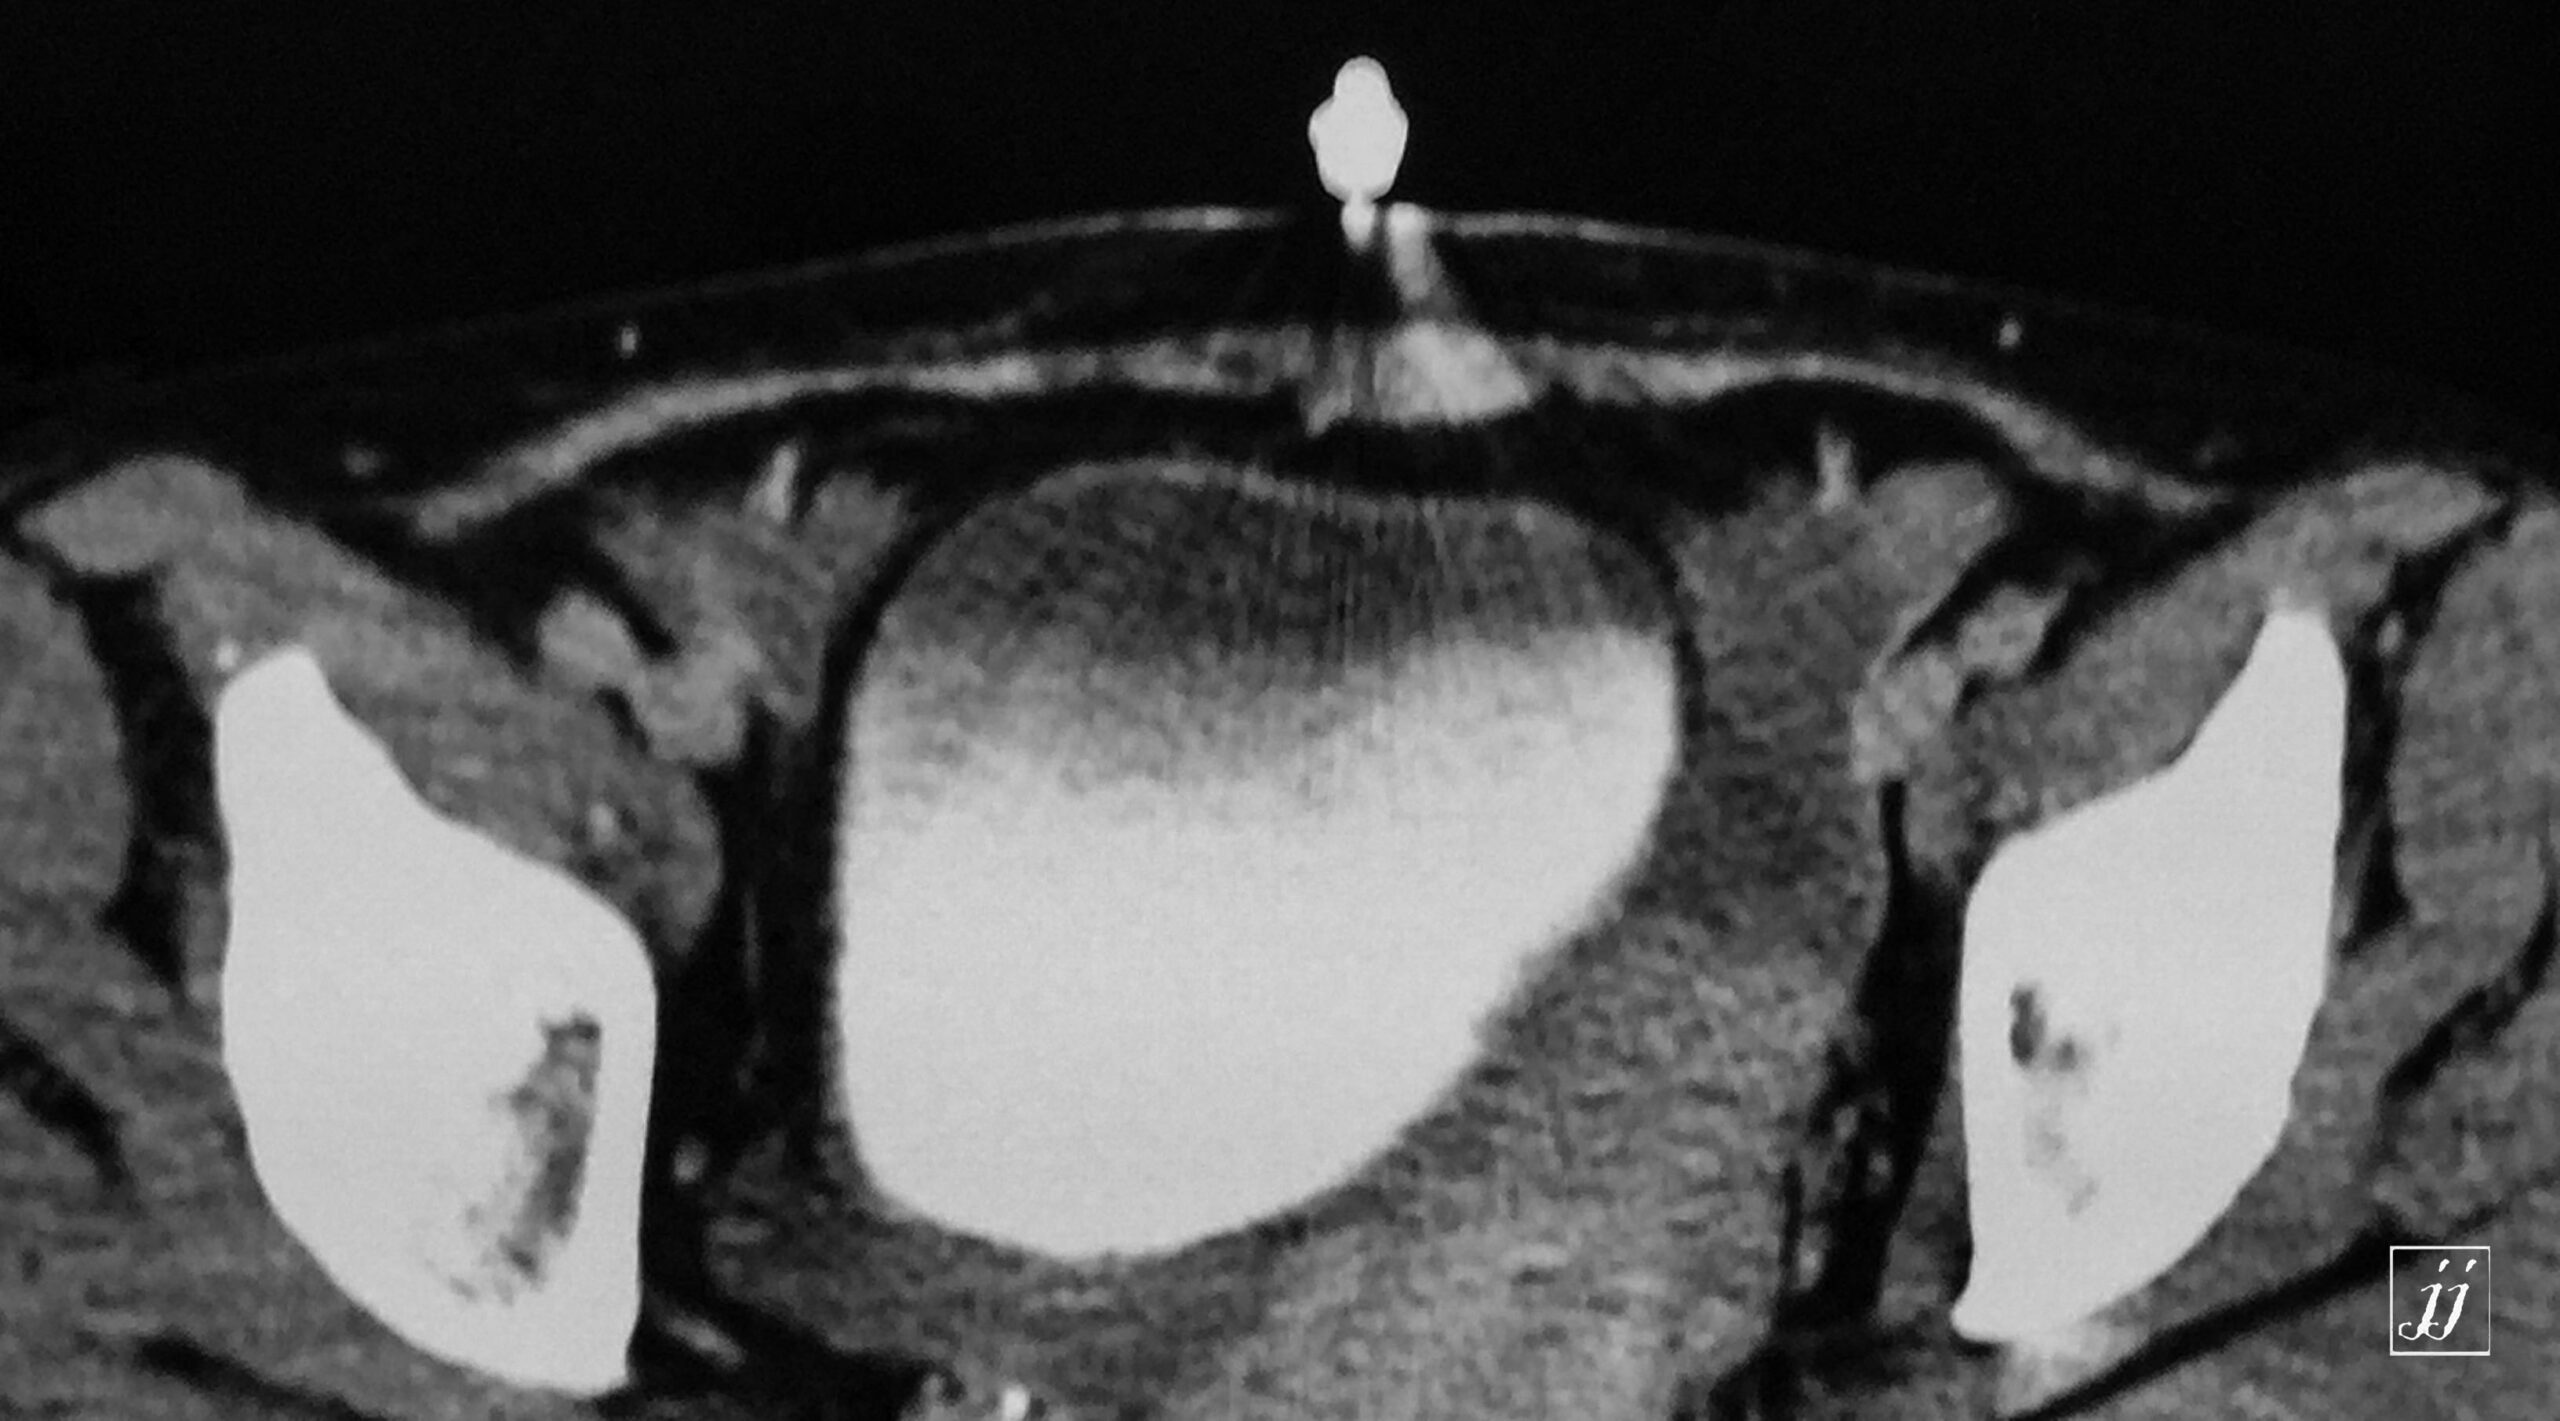

Abdomen- ascites and thick gall bladder wall (3)